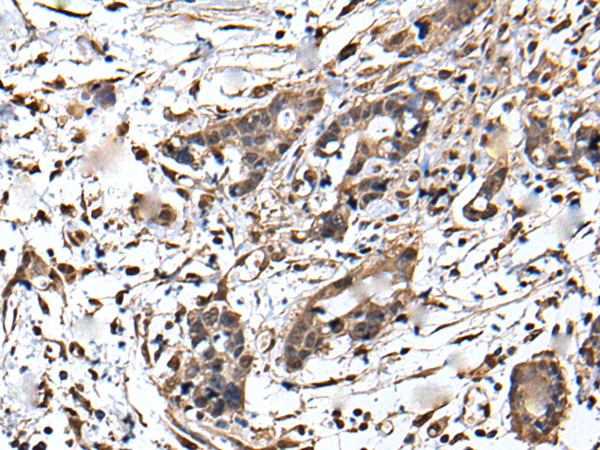

IHC positive control: |

Human brain and human gastric cancer |